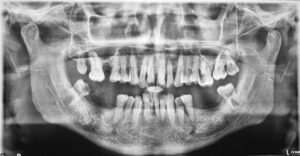

With “CARESTREAM CS-9600” the OPG image quality is one of the finest where almost all details of anatomical region, in any age group can be interpreted to perfection.

PANORAMIC IMAGES IN DIFFERENT AGE GROUPS 👇🏻